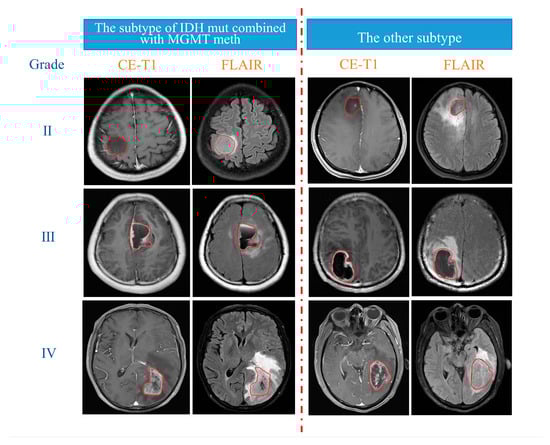

2.4. Tumour ROI Segmentation